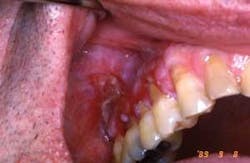

Dispersion throughout the mouth is also found in lichenoid reactions from the use of medications such as non-steoidal anti-inflammatory drugs and anti-high blood pressure medications. Figures 2 and 3 are from a patient who was taking Naprosyn. After discontinuing the medication, the tissue in Figure 3 was noticeably less inflamed. The patient took Tylenol during the two-week period and was later prescribed a different NSAID.